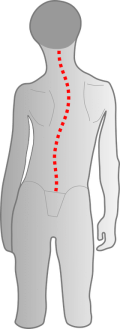

Le problème majeur réside dans la modification de la structure de la tête : la base du crâne devient asymétrique. Cela affecte principalement la position des oreilles (organes de l’équilibre), les articulations temporo-mandibulaires (malocclusion dentaire) et les vertèbres cervicales. La situation devient critique au plus tard lorsque les enfants se redressent à la fin de leur première année et développent une posture asymétrique de la colonne vertébrale.

Les informations erronées provenant des organes de l’équilibre déplacés ou du champ récepteur cervical influencent le traitement dans le cerveau et peuvent entraîner une mauvaise posture de la colonne vertébrale.

La tête est alors intuitivement inclinée, le sens du corps ne se développe pas correctement, ce qui a des répercussions sur le développement moteur et la perception corporelle.

Si l’ajustement des vertèbres supérieures n’est pas correct, cela peut entraîner une déformation de la colonne vertébrale.